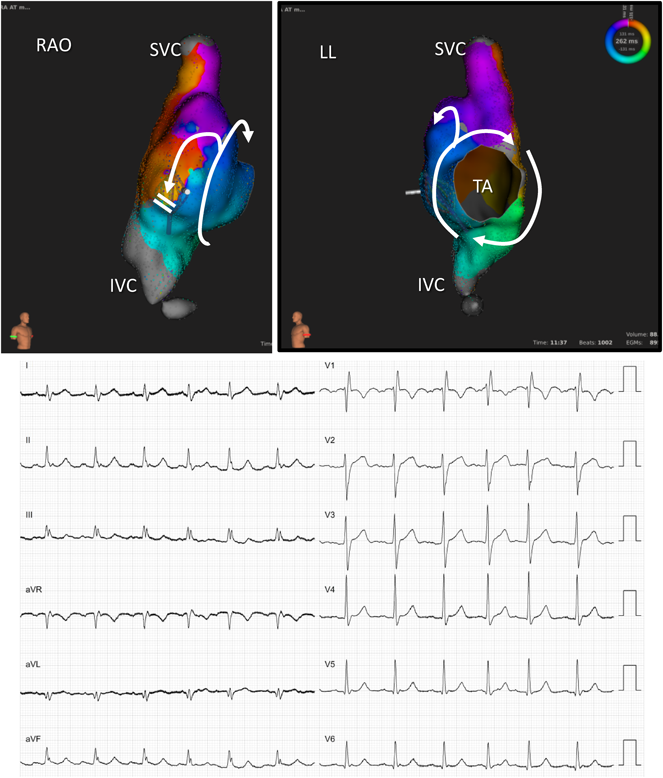

Pediatric Cardiology and Cardiac Surgery 33(5): 385-394 (2017)

Fig. 3 Activation pattern of uncommon intra-atrial reentrant tachycardia in a patient with repaired tetralogy of Fallot via a three-dimensional electroanatomical mapping system using Rhythmia (Boston Scientific, Cambridge, MA). The activation propagated clockwise around the tricuspid annulus and in the superior-to-inferior direction on the posterior side of the incision

IVC, inferior vena cava; LL, left lateral; RAO, right anterior oblique; SVC, superior vena cava; TA, tricuspid annulus